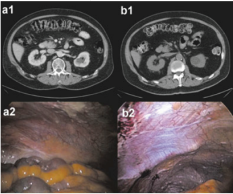

Peritoneal karsinomatozisin ( karın içi yaygın kanser ) teşhisi zordur. Bilgisayarlı tomografi, MR gibi görüntüleme teknikleri, cerrahi girişimin planlanmasını sağlayabilir. Bunun ötesinde yararı olmayacak bir ameliyatın yapılmasının da önüne geçmiş olur.Ancak bu tetkikler , küçük volümlü hastalığın tanısında sensitivitesi düşük olduğundan, lokalize peritoneal karsinomatozisin saptanmasında yetersiz kalabilir.Dolayısıyla peritoneal karsinomatozisin tanısında laparoskopi veya laparotomi ile peritonun ( karın zarı ) direkt olarak görülmesi “ Altın Standart” tır.

Peritoneal kanseri bilinen veya şüphe edilen hastalarda görüntüleme çalışmaları esastır.Son yıllarda görüntüleme tekniklerinde önemli gelişmeler olmasına rağmen, peritoneal yayılımın yeterince tespiti, kitlelerin boyu, morfolojisi ve lokalizasyonu nedeniyle zaman zaman güç olmaktadır.

Küçük peritoneal tutulumların ortaya konmasında doğruluğu sınırlı kalmakla birlikte, Kontrast-enhanced Bilgisayarlı tomografi, peritoneal karsinomatozisin ( karın zarı kanser yayılımı ) tanısında standart görüntüleme yöntemidir. Bununla birlikte, 5 mm.den küçük lezyonlarda % 30- 45 oranında gözden kaçma riski bulunmaktadır.

5.Tanısal Laparoskopi: Peritoneal karsinomatozun yaygınlığının ameliyat öncesi dğderlendirilmesi zordur, net bir değerlendirme sıklıkla cerrahi eksplorasyon esnasında yapılır. Klasik görüntüleme yöntemleriyle evreleme çoğu kez sınırlı kalabilir, bu durumda yanlış evreleme yada gereksiz laparotomi ( kesi yapılarak karnın açılması ) gündeme gelebilmektedir. Diagnostik ( Tanısal ) laparoskopi, karın içi kanser ile ilgili detaylı bilgi edinme yanında peritoneal karsinomatosiz şüphesinin histolojik teyidi için önemli katkı sağlar.Ayrıca uygulana neoadjuvan ( ameliyat öncesi ) kemoterapinin etkilerini değerlendirmede etkin olarak kullanılabilir.

Karın 37 0 C sıcaklıkta karbondioksitle şişirildikten sonar iki adet balonlu trokar ( Applied Medical ) karın duvarına yerleştirilir. Karın içi laparoskopik olarak eksplore edilir ( tümüyle görüntülenerek incelenir ) ve peritoneal kanser indeksi ( PCI ) belirlenir. Assit boşaltılır ve karın duvarından biopsiler alınır. Nebulizer ( MIPR , Reger Medizintechnik) yüksek-basınç enjektörüne ( Injectron 82M ,MedTron ) bağlanır ve trokardan geçirilerek karın içine yerleştirilir.